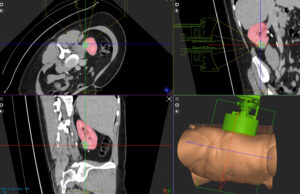

Histotripsy is a non-thermal, non-ionising and non-invasive focused ultrasound technique which relies on cavitation for mechanical tissue breakdown at the focal point. Leading research...